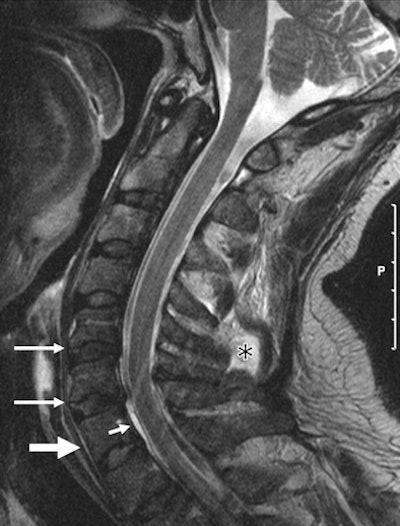

| MR image of a 46-year-old man who was imaged within 48 hours after a motor vehicle injury. Sagittal T2-weighted image shows a focal hematoma (*) and trace of prevertebral hemorrhage (thick arrow). A rare epidural hematoma is also evident (short thin arrow). Image courtesy of Radiology. |

The data also showed some significant differences between the two groups. The MRI scans revealed 24 findings of occult vertebral fractures in eight whiplash-injury patients and one finding in one control subject. In addition, there were 126 findings of vertebral body contusions in 17 patients and 42 findings in 13 control subjects, and 95 findings of muscle strain in 21 patients and 14 findings in nine control subjects.

MRI also showed nine muscle tears and/or hematomas in one patient and no such results among the control subjects. There were also 46 findings of perimuscular fluid in four patients and two such findings in one control subject.